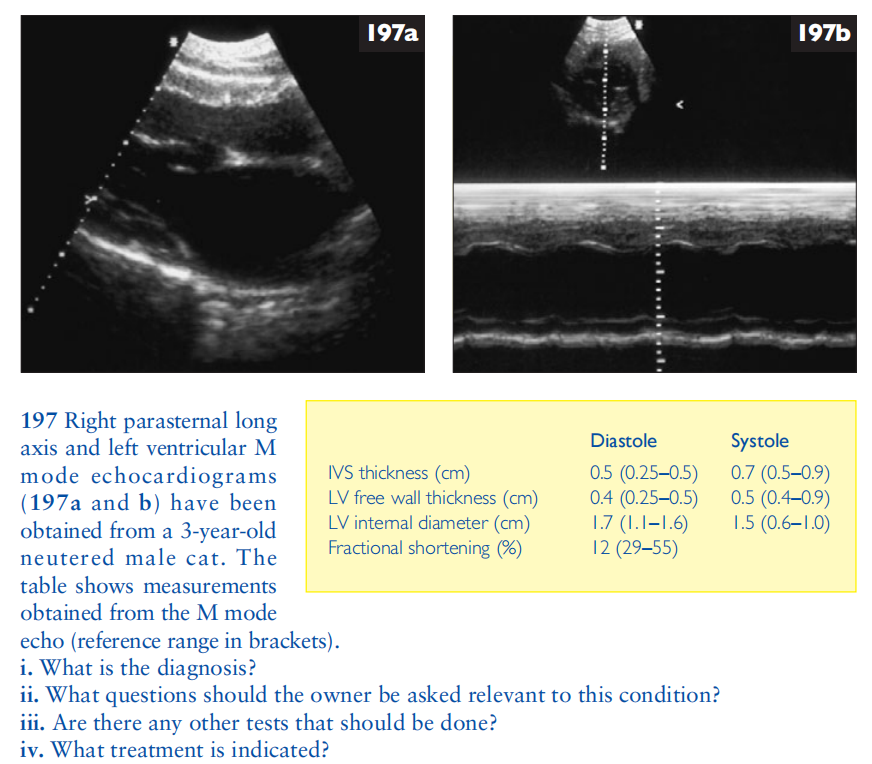

翻译:祁海丽;校对:石慧16 A 6-year-old castrated male Maine Coon cat presents with severe r...